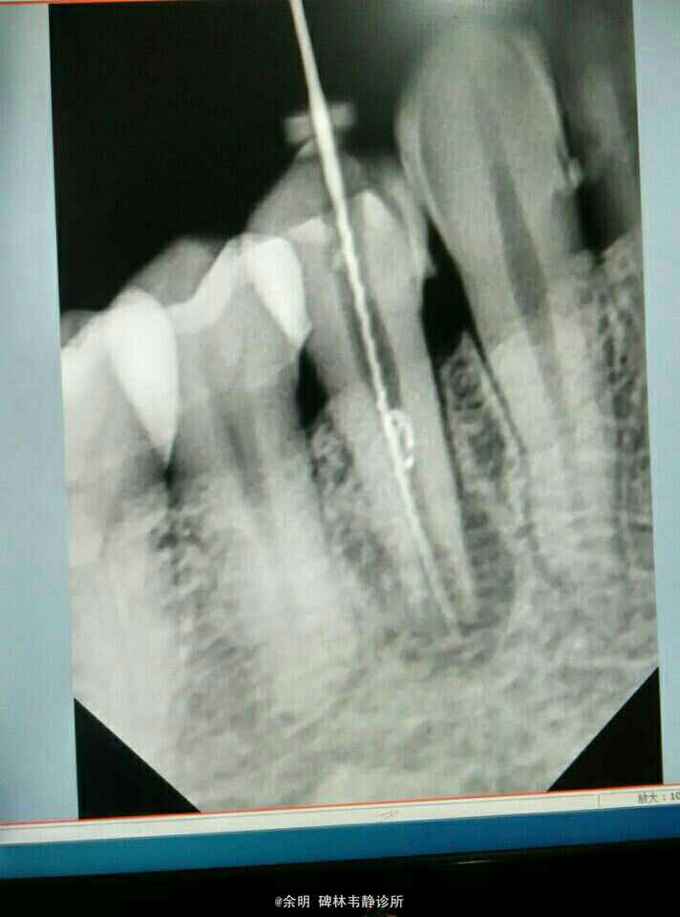

44白色暂封物(去除后可见棉捻),颊侧牙龈可探及瘘管及白色脓性分泌物,叩(+);X线片示:根管口成“喇叭状”,根管中段内可见白色物,根尖阴影。

根尖周炎?根裂?牙内吸收? 处理:44去除暂封料及棉捻,清理髓腔,H2O2.NC冲洗,取出根中白色充填物,隔湿消毒干燥后,手调氢氧化钙暂封 第二次 复诊:44颊侧瘘管未消失,白色脓性分泌物消失,叩(_)。 处理:44去除暂封料,H2O2.NC冲洗,隔湿消毒干燥后,手调碘仿及氢氧化钙暂封。 医嘱:根充后常规医嘱,不适随访。

这个病例还未处理完成,拿出来与大家讨论讨论。 1畸形中央尖一般大都有对称性,检查拍片未见34有中央尖 2牙根纵折早期有冷热痛,咀嚼痛(病人的未有这些症状)(附根纵折的资料), 3根内吸收可见牙冠成粉红色,此病人牙冠未变色 我发出来这个病例:想和大家交流交流,望大家多给宝贵意见,留下这颗牙。